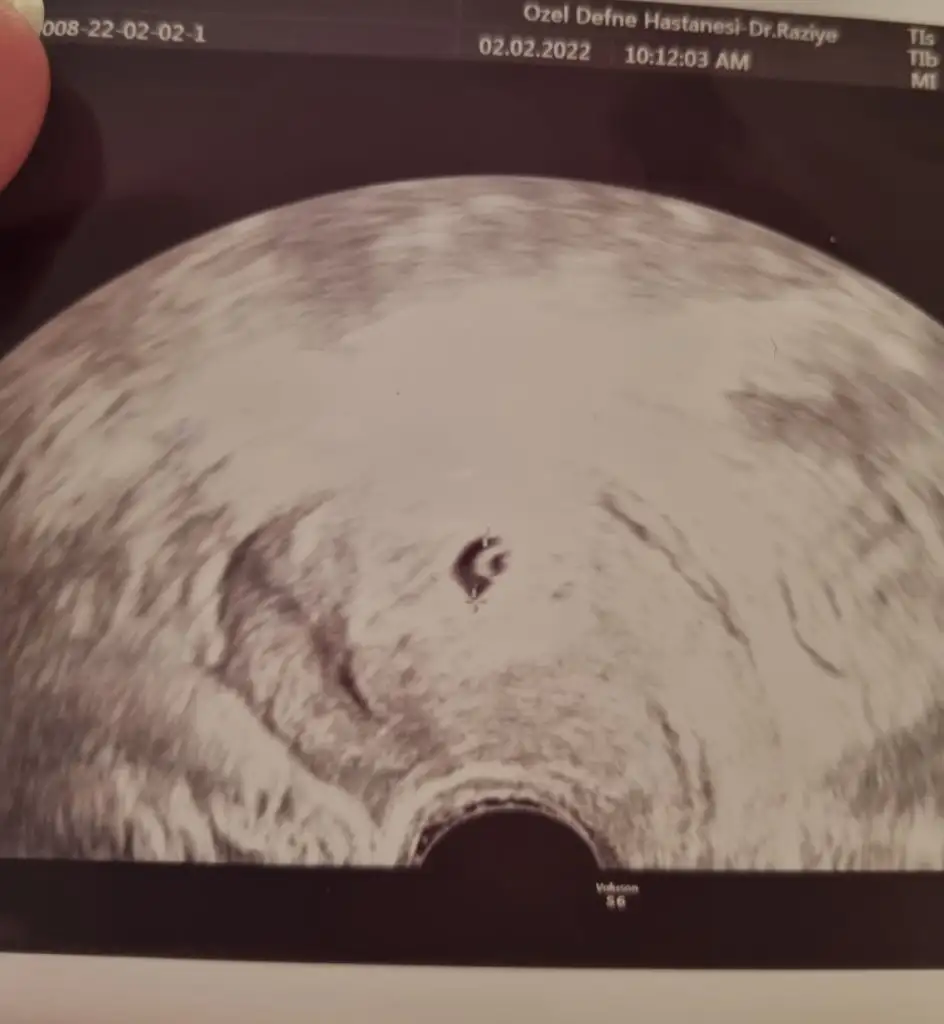

O kadar da baklısın ki, iradem de tamdır bu konuda, yıllarca içmediğim oldu aramadım hiç, bebek mi istiyor acaba beybisi?O kadar uğraş bebek yap her gün iğne yap sonra çocuğu dumana boğ..çık çık çık hiç yakıştıramadım canım morarmış koluna bak canın sigara çekince